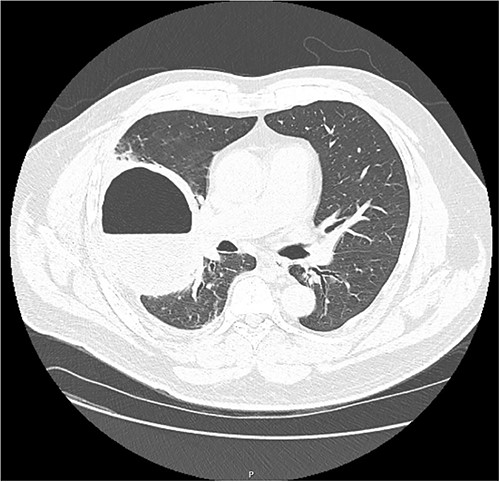

On examination, he appeared well, with no oxygen requirement and reduced air entry in the right mid to lower chest. A chest X-ray (Fig. 1) showed a large cavitating lesion in the right lower zone with a chest computed tomography (CT; Fig. 2) confirming a large lung lesion measuring 100 mm × 80 mm × 100 mm with surrounding ground glass changes. Tests for SARS-CoV-2 and hydatid serology returned positive. He proceeded to have a bronchoscopy and bronchoalveolar lavage that was negative for aspergillus, galactomannan, mycobacterial and fungal cultures, cryptococcus, respiratory viral panel and cytology. A CT abdomen (Fig. 3) revealed multiple hepatic cysts with the largest measuring 59 mm in size in the right lobe. Given the findings of lung and liver lesions, he was commenced on albendazole for presumed extra-hepatic hydatid disease and referred to the cardiothoracic team for resection of the pulmonary hydatid cyst.